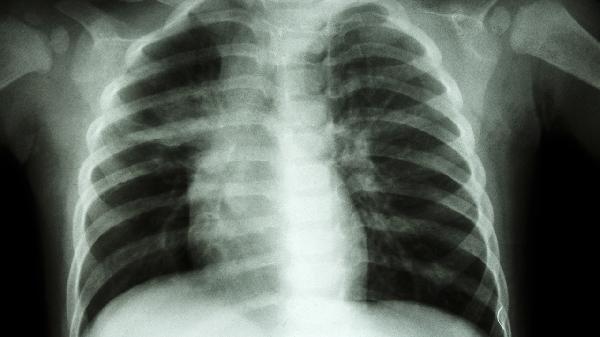

出现右肋骨下方吸气疼痛时,建议避免剧烈运动及突然转身动作。睡眠时选择健侧卧位,用枕头支撑患侧减轻压力。饮食宜清淡,胆囊疾病患者需限制油腻食物。疼痛持续超过3天或伴随发热、黄疸、呼吸困难等症状,须立即就诊完善胸片、超声等检查。恢复期可进行肩关节环绕等低强度活动,防止胸廓僵硬。